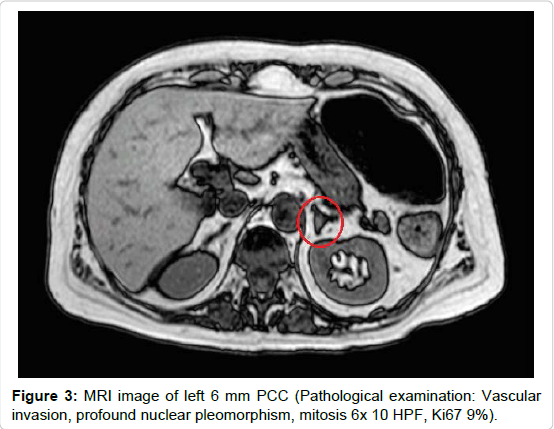

However, despite normalization of coagulation parameters, renal function and LVEF, high levels of direct bilirubin persisted, and patient developed sub-icterus. An abdominal echo scan was then performed, identifying dilated biliary ducts, without hepatic masses or alterations; kidneys were normal, but a right adrenal incidentaloma was discovered. To confirm the diagnosis for biliary tract pathology, an MRI diagnosed the presence of an ampulloma (20 mm) but it also evidenced left (6 mm) and right (40 mm) masses of adrenal glands (Figures 1, 2 and 3). High concentrations of urine and plasma free metanephrines (p-normetanephrines: 1518 and 2480 pmol/L, p-metanephrines: 3313 and 4222 pmol/L, u24h-normetanephrines: 437 and 509 mcg/die, u24h-metanephrines: 1386 and 1830 mcg/die), high Chromogranin A (>1100 ng/mL) and neuron specific enolase (19.6 ng/mL) levels suggested the diagnosis of pheochromocytoma (PCC). The presence of distant metastasis was excluded with brain-neck-thoracic CT scan and with 123I-MIBG and 111In-Pentetreotide Scintigraphies. Both imaging methods showed surprisingly a more intense tracers’ uptake from left PCC without visualizing the ampulloma.

Figure 3. MRI image of left 6 mm PCC (Pathological examination: Vascular invasion, profound nuclear pleomorphism, mitosis 6x 10 HPF, Ki67 9%).

All tumors were surgically removed without complications. Pathologist confirmed the diagnosis of bilateral PCC (right adrenal gland: PCC of 40 mm, Ki67 2%; left adrenal gland: PCC of 5 mm with vascular invasion, profound nuclear pleomorphism, mitosis 6x 10 HPF, Ki67 9%) and of ampullary neuroendocrine tumor (G2 with muscular invasion – pT2 N0 M0). Results from genetic analysis confirmed the mutation in NF-1 gene. After 3 year of regular follow-up, the patient presents good clinical conditions and has neither biochemical nor radiological evidence of disease recurrence.